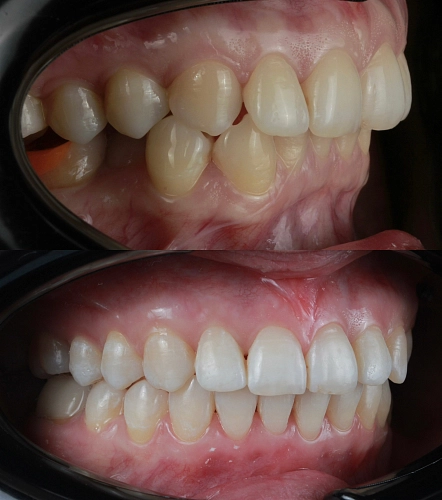

Клинический случай:

Рассмотрим пример ортодонтической коррекции на брекет-системе Damon Q. В данном случае срок лечения составил 1 год и 10 месяцев. За этот период удалось решить несколько важных задач:

• Устранение скученности зубов

• Коррекция наклона верхнего зубного ряда

• Удаление сильно разрушенного зуба на нижней челюсти и закрытие образовавшегося промежутка своими зубами

• Откорректированный прикус и центры зубных рядов

Работа была выполнена врачом-ортодонтом Глуховой Т.А., который тщательно подошел к каждому этапу лечения, чтобы достичь оптимального результата.